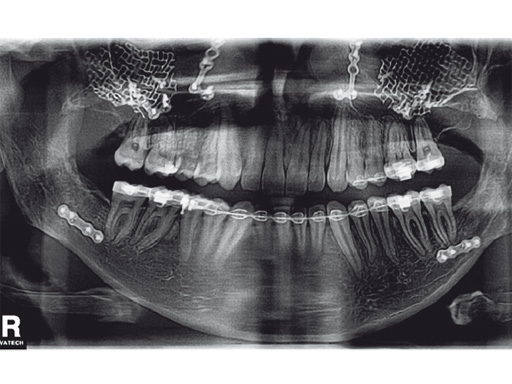

Case 1: Camouflaging of deficient zygomatic prominences by mesh augmentation. a 19-year-old man with a typical-angle class iii appearance is shown preoperatively (fig 4a) and postoperatively (fig 4b). after preoperative planning, a bimaxillary osteotomy with advancement of the upper jaw and backwards movement of the lower jaw following bisagittal split osteotomy was performed. alternative options to augment the malar bone are surgical osteotomy of the malar bone with outwards movement of the zygomatic prominences, high le fort i osteotomy with onepiece movement of the maxilla together with the zygomatic prominence, using other biomaterials than meshes to augment these prominences. in this case, the average prominence in an adult caucasian patient was mimicked by contouring a 0.6 mm thick, 3-D mesh using the artificial skull.